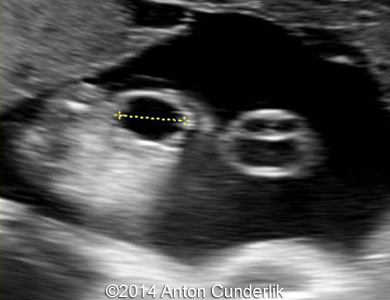

Our examination revealed a cystic, biloculate structure within fetal tongue. MRI imaging confirmed the finding. The newborn was delivered at term via cesarean section (male, 3210 g, 50 cm, Apgar score 10/10).

Image 2, 3, 4, 5, 6, 7: 30 weeks of gestation; the images show cystic structure within the fetal tongue that later turned out to be thyroglossal cyst.